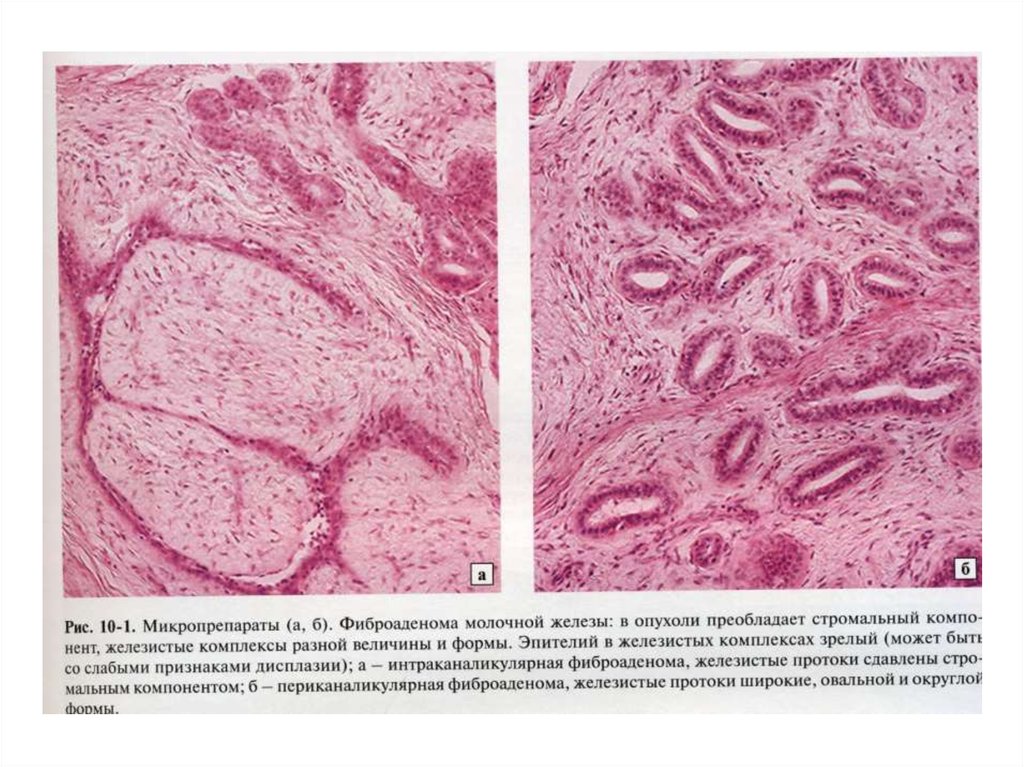

Исследование: микропрепарат молочной железы в медицине

Раздел: Снимки-откровения